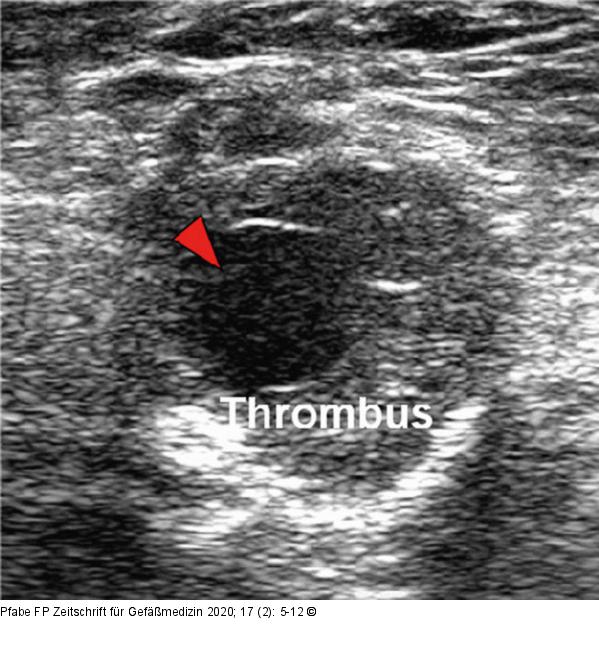

Abbildung 4: PAA im Gefäßultraschall PAA von 34 mm Durchmesser im Gefäßultraschall (B-Mode). Freies Lumen (roter Pfeil) umgeben von einem wandständigen, zirkulären Thrombussaum. |

PAA von 34 mm Durchmesser im Gefäßultraschall (B-Mode). Freies Lumen (roter Pfeil) umgeben von einem wandständigen, zirkulären Thrombussaum. |